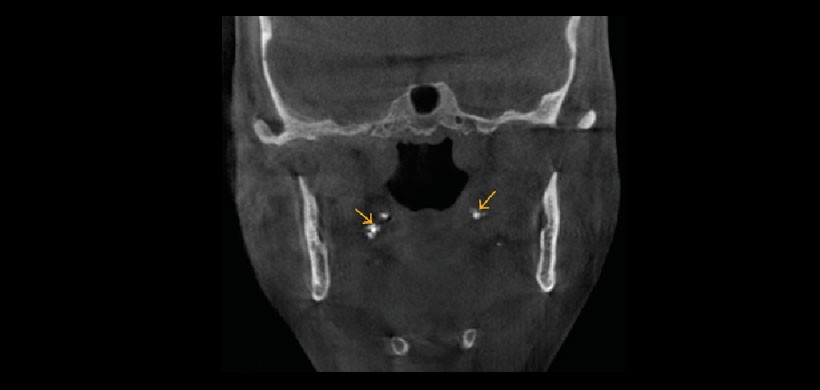

Fig 1. Tomografía volumétrica, vista coronal. Muestra la presencia d tonsilolitos (Calcificaciones en tejidos blandos, asociado a procesos infecciosos de las amígdalas palatinas, importante su evaluación para la interconsulta con el médico otorrinolaringólogo.